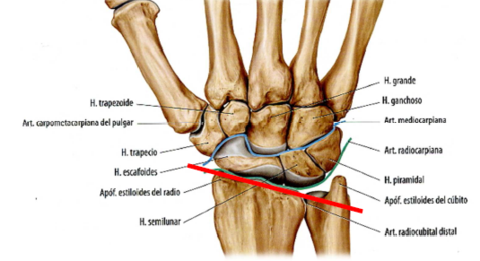

Condílea: Es biaxial, movimientos en 2 planos (Sagital y coronal). forma elipsoidea. Ejemplo: Radiocarpiana.

Encaje recíproco: Es biaxial, movimientos en 2 planos (Sagital y coronal), forma en silla de montar. Ejemplo: Trapeciometacarpiana.